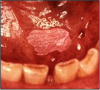

Leukoplakia: A precancerous lesion of the oral soft tissue that consists of a white patch or plaque that cannot be scraped off (Figure 3). It is often associated with tobacco use. It can persist in an area with no pain or irritation. These areas can develop into more serious lesions and should be examined carefully during a meticulous oral evaluation. Some leukoplakia will regress if tobacco use is discontinued.

Leukoplakia: These can lead to aggressive oral cancers if left unchecked. The lesion pictured below (Figure 5) is a very early lesion with a rather thin coating of leukoplakia which should resolve with cessation of snuff use.

Verrucous Carcinoma: The longer snuff is used, the thicker and whiter the leukoplakia becomes and the more likely the lesion is to transform into an aggressive form of squamous cell carcinoma known as verrucous carcinoma. In most cases, cessation of the habit prior to the development of the cancer results in the disappearance of the lesion and a return to normal mucosa.35